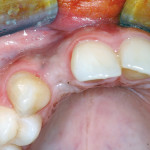

Complicanze in un caso di innesto di osso autogeno a blocco e loro successiva...

Gli impianti dentali possono essere considerati come una delle principali innovazioni nella moderna Odontoiatria. Con il miglioramento della metodologia e della tecnologia, il successo...